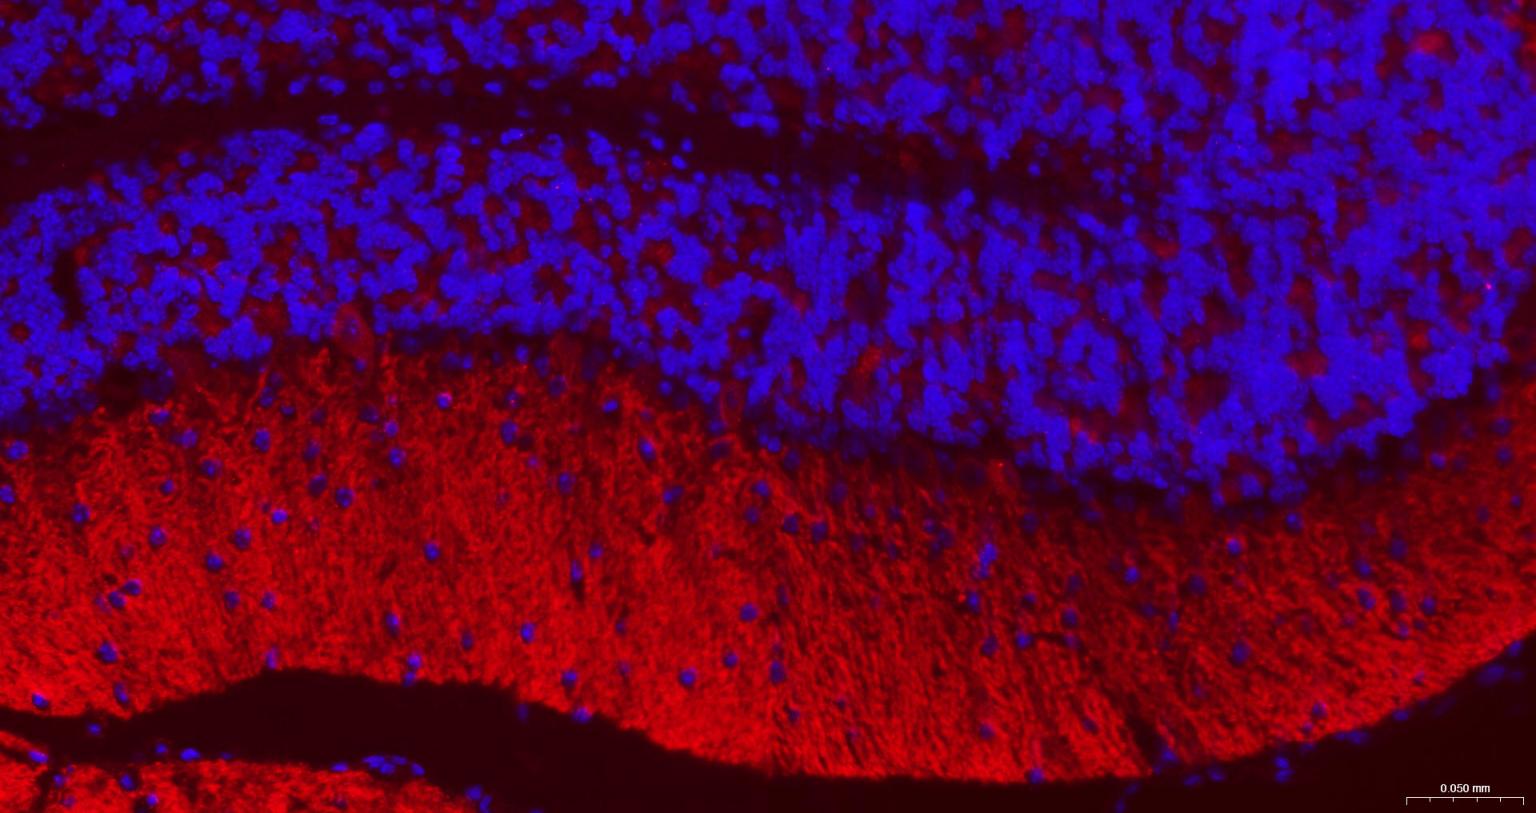

IHC-FHuman, Mouse, Rat1:50-200

IFHuman, Mouse, Rat1:50-200

组织特异性

Highly expressed in brain, especially in cerebral cortex, thalamus, hippocampus, frontal, occipital and temporal lobe, occipital pole and cerebellum, followed by corpus callosum, caudate nucleus, spinal cord, amygdala and medulla. Weakly expressed in heart, testis and skeletal muscle.